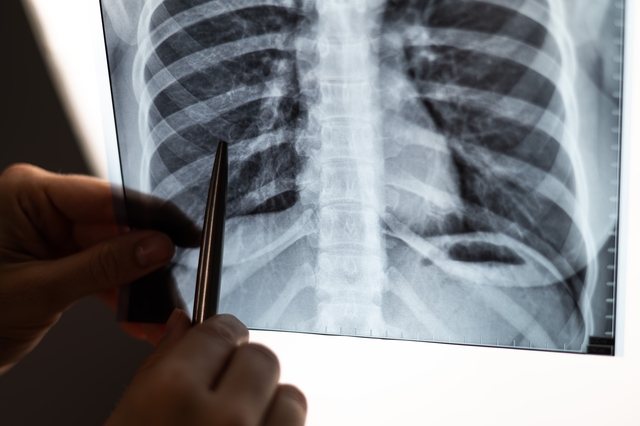

Akciğer kanseri, sık görülen ve kansere bağlı ölümlerin başlıca nedenlerinden biri olarak ülkemizde ciddi bir halk sağlığı sorunu oluşturuyor. Tıbbi Onkoloji Uzmanı Doç. Dr. Murat Sarı, bu hastalığın erken evrede tespit edilmesinin tedavi sürecinde belirleyici bir rol oynadığını ifade etti. Akciğer kanseri riskini artıran en önemli etkenin sigara kullanımı olduğunu vurgulayan Doç. Dr. Sarı, sigara içen bireylerin tarama programlarına düzenli olarak katılmasının hayati önem taşıdığına dikkat çekti.

AKCİĞER KANSERİNİN YAYGINLAŞAN RİSKLERİ